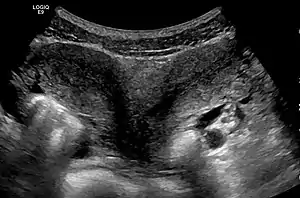

Diagnosis

Besides a physical examination, the physician will need imaging techniques to determine the character of the malformation: gynecologic ultrasonography, pelvic MRI, or hysterosalpingography. A hysterosalpingogram is not considered as useful due to the inability of the technique to evaluate the exterior contour of the uterus and distinguish between a bicornuate and septate uterus. In addition, laparoscopy and/or hysteroscopy may be indicated. In some patients the vaginal development may be affected.